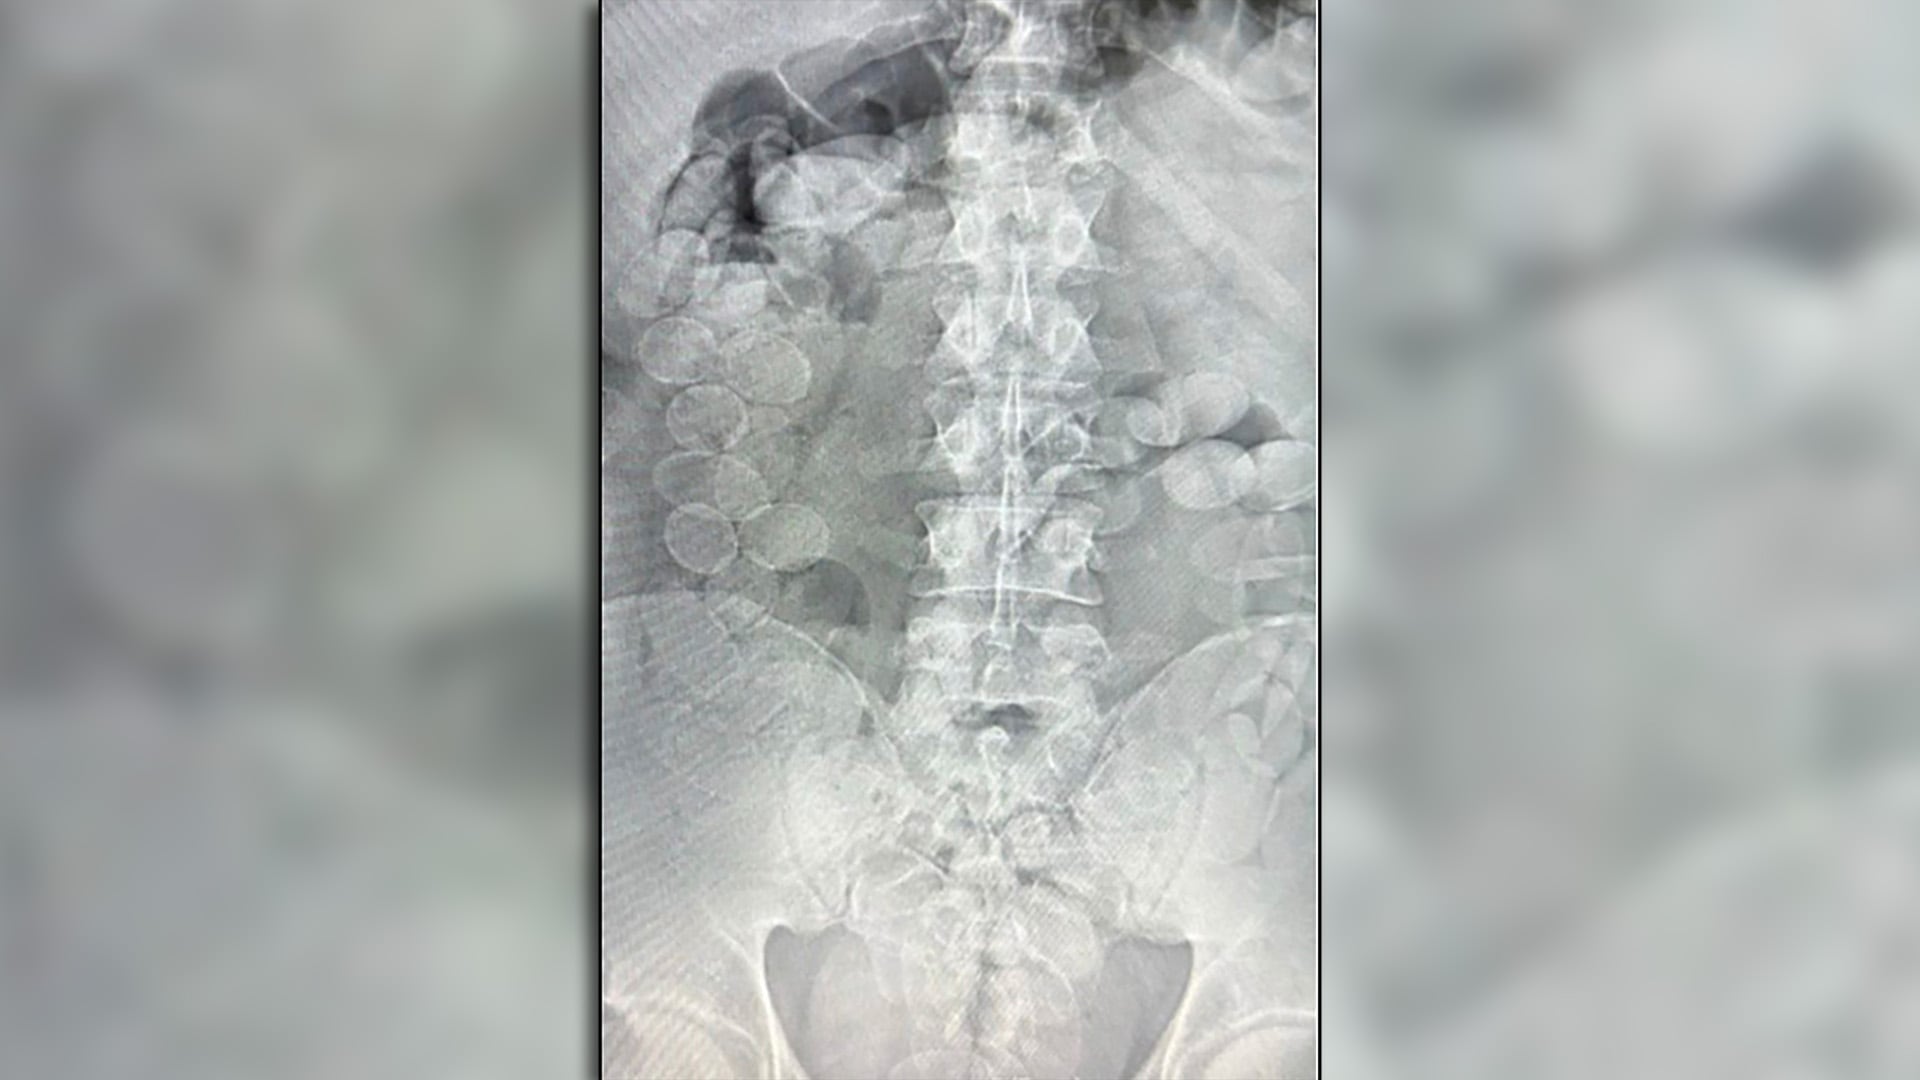

Según reportó el MPF, ambos acusados manifestaron malestar físico y admitieron que habían ingerido cápsulas con estupefacientes. En consecuencia, fueron trasladados al Hospital de Ceres, donde estudios radiográficos confirmaron la presencia de cuerpos extraños compatibles con cápsulas.

Finalmente, expulsaron un total de 185 envoltorios con cocaína: 93 de Sirilo Quispe Carmona (27 años) y 92 de Abel Rocha Risco (28 años), con un peso total de 2.451,3 gramos y una pureza promedio del 85,17%.